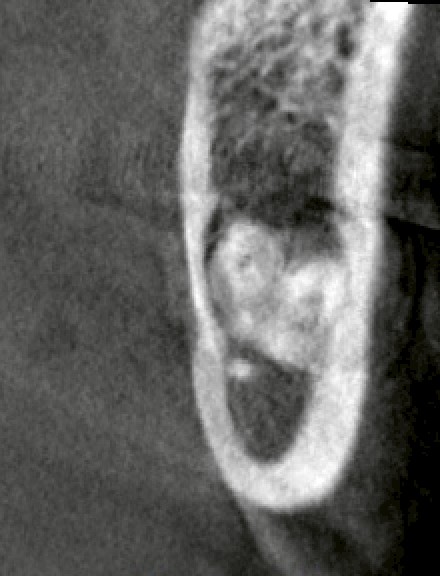

CTにて確認したところ、

・下顎:深い完全埋伏

・歯根は明らかに湾曲

・下歯槽神経に近接〜一部接触所見

・上顎:完全埋伏

・上顎洞に極めて近接

という状況でした。

いずれも「難易度が低い」とは言えないケースです。